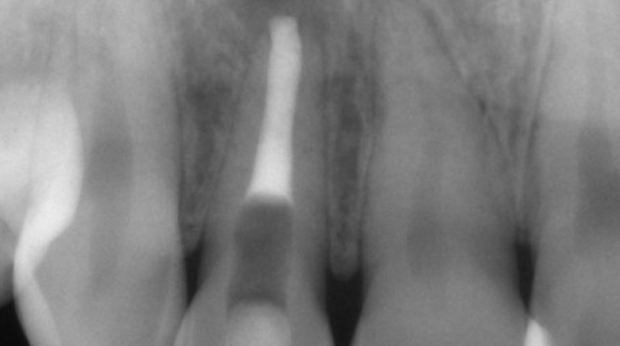

임플란트와 사랑니 발치는 외과적 시술로 잇몸을 절개하는 외과적 시술은

짧으면 짧을 수록 시술 후 붓기와 통증이 최소화됩니다.

치과의사 경력 14년차 구강외과 전문의가 빠르고 안전하게, 아프지 않게 수술해 드립니다.